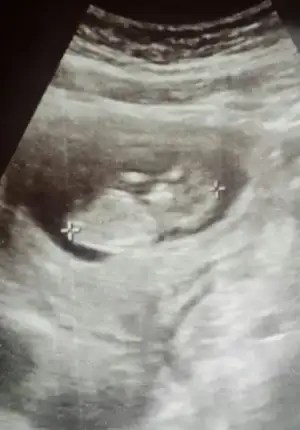

Cnm senin cimsiyet belli oldu mu kesin kızmı ?